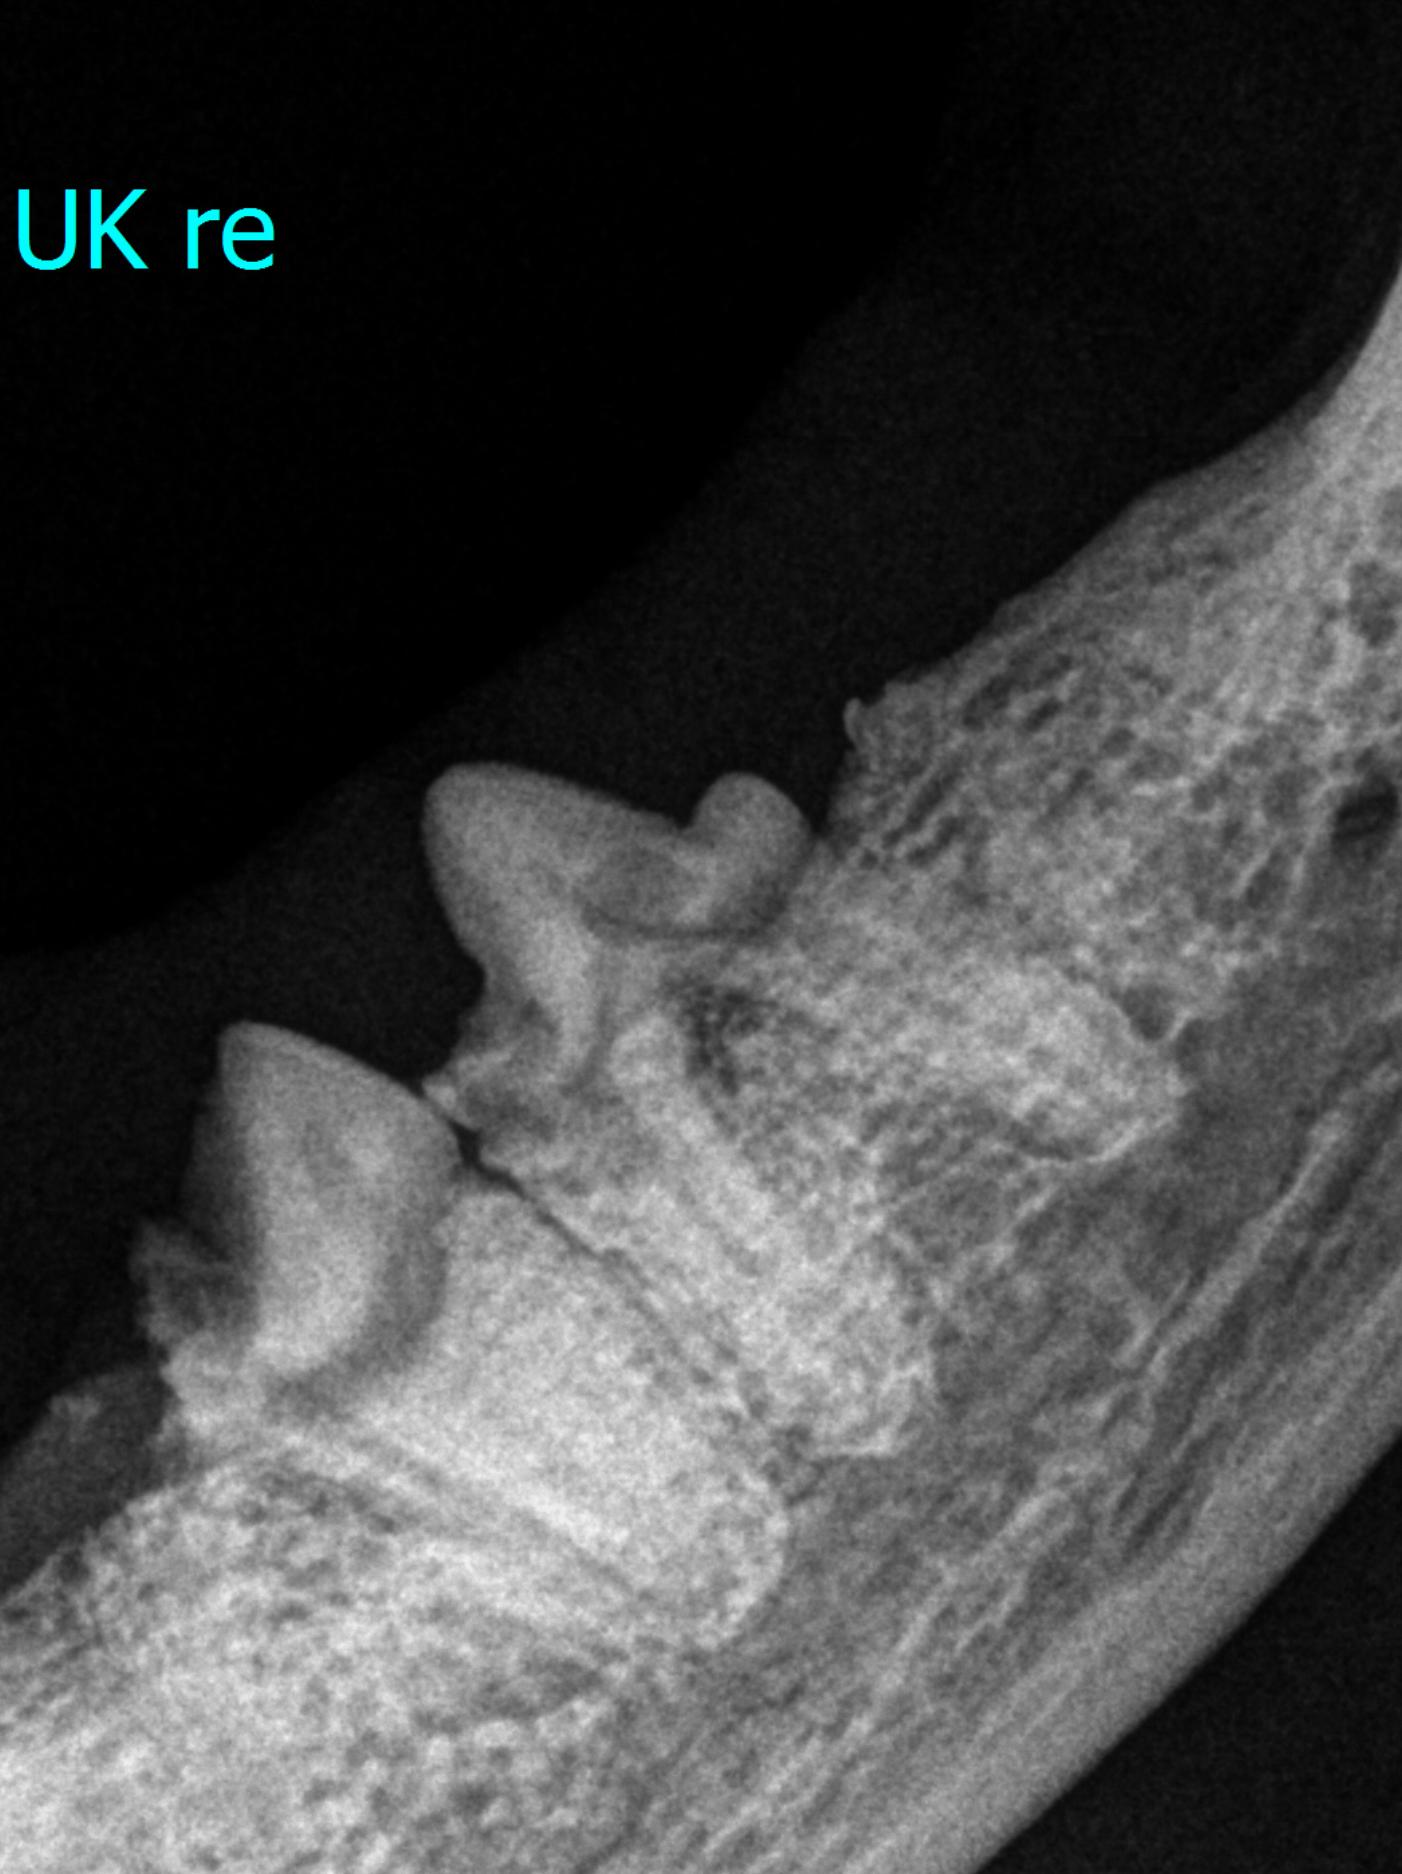

Zur Diagnostik von dentalen und Kieferproblemen liefert die Röntgen-Diagnostik mittels starrer oder Dentalradiographie einen essentiellen Beitrag. Das Erstellen der entsprechenden Bilder ist der technische Beitrag, welcher bei der E. Schweizer AG als Lagerungskurs für die für TierärztInnen und TPA geschult wird. Die Interpretation ist der zweite Schritt. Zu diesem Zweck wird ein Webinar für die Interpretation von Zahn- und Kieferbildern angeboten. Dabei werden die radiologischen Befunde und entsprechenden Diagnosen erhoben. Zusätzlich wird auch ein Therapieplan aufgestellt. Die relevanten Krankheitsbilder sind FORL (TR), feline chronische Gingivostomatitis, Zahn- und Kieferfrakturen, Wechselprobleme, Zucht-relevante Befunde, Neoplasien und vieles mehr. Damit liefert dieser intensive Abendkurs einen direkten Beitrag für den klinischen Alltag

| 2020 - 2040 | Die wichtigsten Pathologien im Dentalröntgenbild |

| 2040 - 2115 | Fälle zum Studieren |